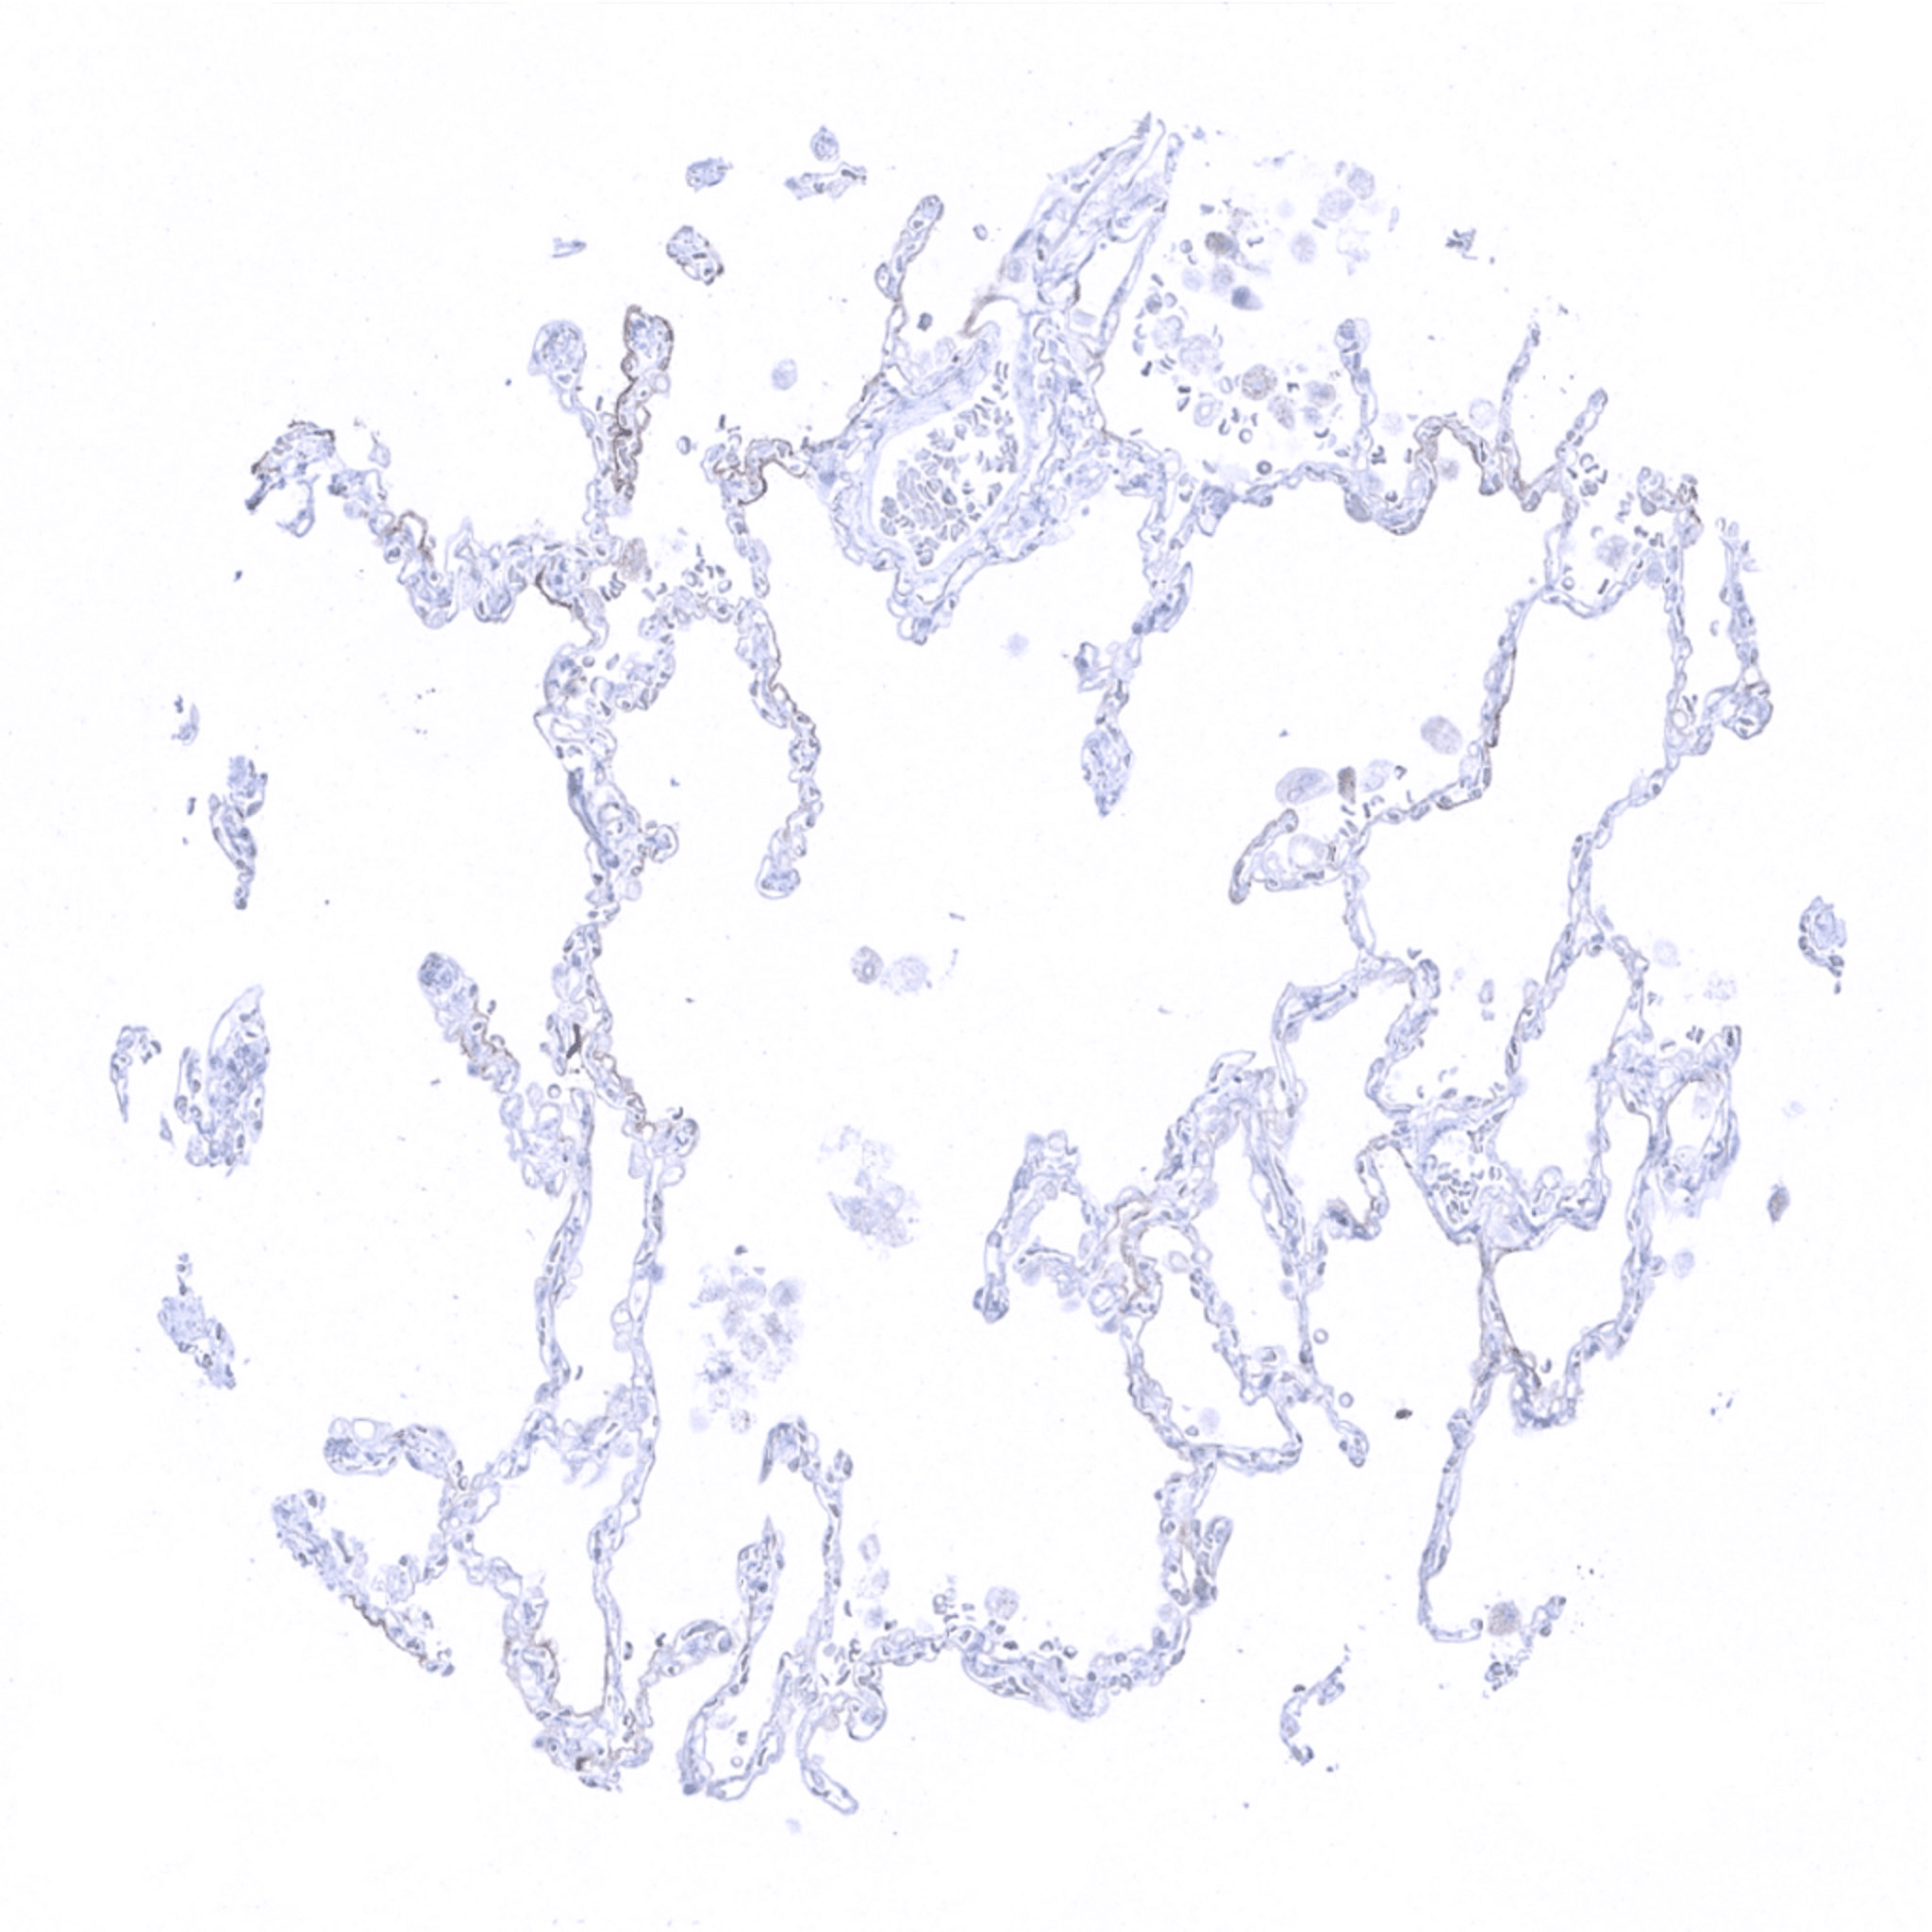

Lung